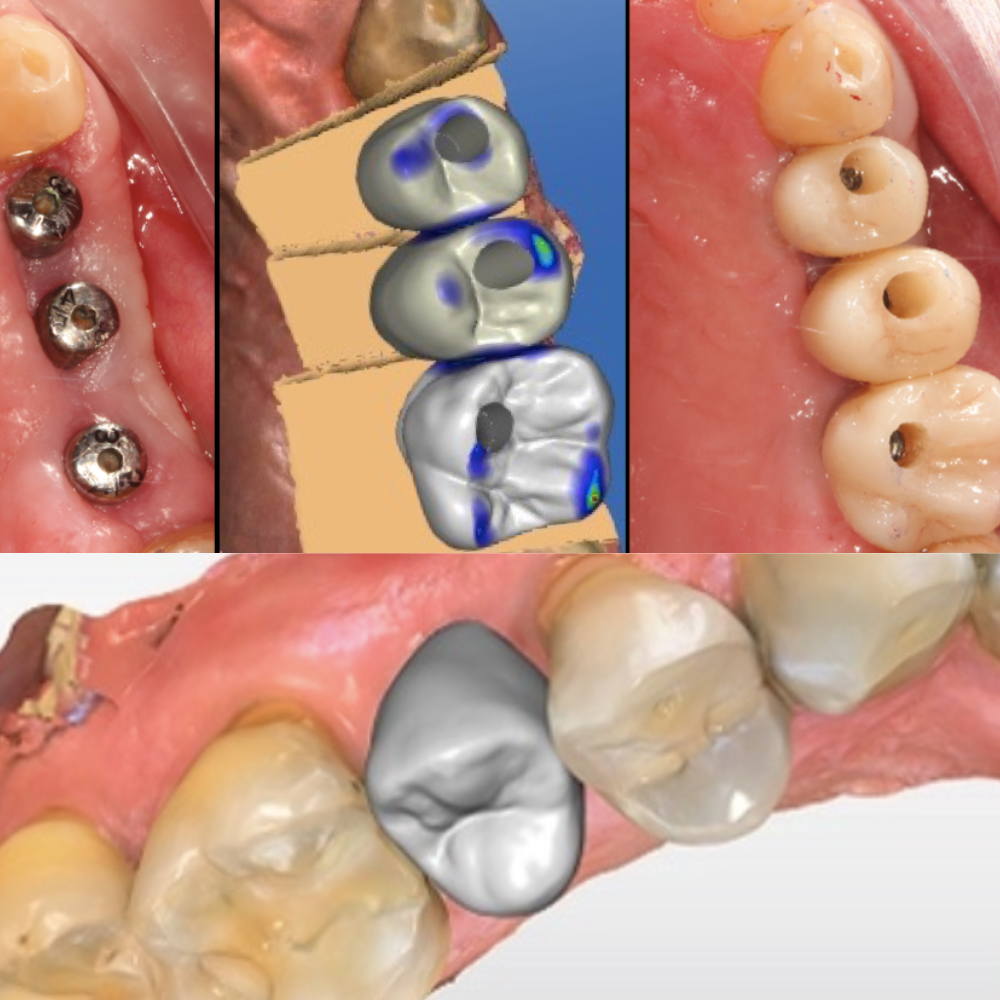

En nuestra clínica contamos con un Laboratorio Digital Dental propio, equipado con tecnología de última generación que nos permite diseñar y fabricar tratamientos con máxima precisión, rapidez y estética.

🔹 Escáner digital

🔹 Software de diseño CAD/CAM

Permite planificar y diseñar digitalmente cada restauración, logrando resultados personalizados y altamente estéticos.

🔹 Fresadora dental

Fabricación automatizada de coronas, carillas y otras rehabilitaciones con exactitud milimétrica.

- Coronas y puentes

- Implantes y guías quirúrgicas